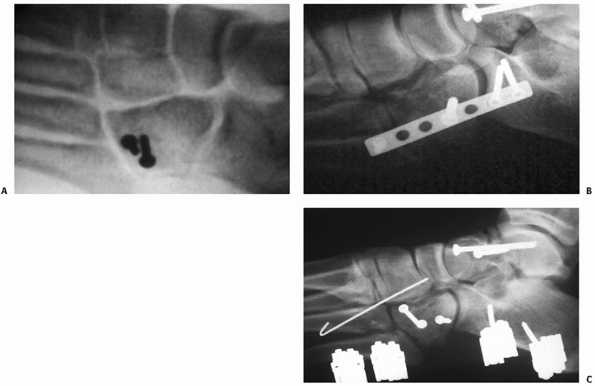

![]() |

FIGURE 60-15

Surgical approach to the cuboid. Palpable landmarks are the sinus tarsi and the fourth tarsometatarsal joint. The incision should be dorsal to the sural nerve and plantar to the extensor brevis muscle. |

FIGURE 60-16 Restoration of nutcracker fracture of cuboid. A. Typical fracture appearance in anteroposterior and lateral planes. B. Placement of external fixator to restore normal anatomy. Any defect should be filled with cancellous graft. C. Internal stabilization is possible with a 3.5-mm tubular plate to maintain reduction and position of cuboid.

|